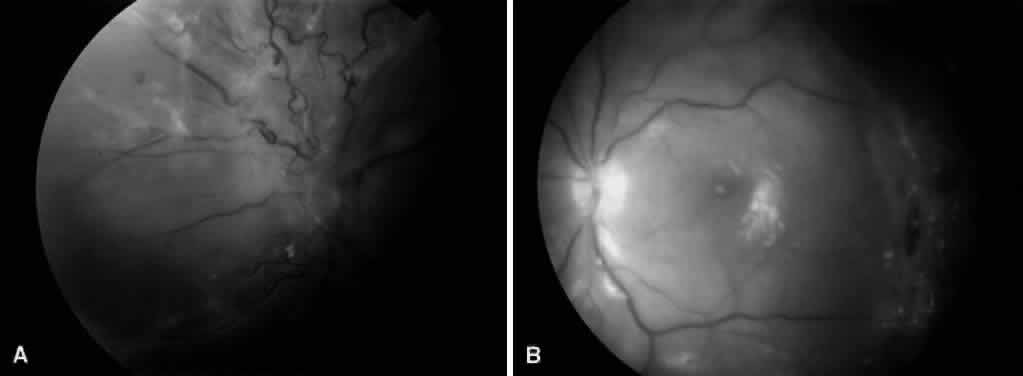

Fig. 7. A. Preoperative fundus photograph of an eye with recurrent combined retinal detachment from proliferative diabetic retinopathy and proliferative vitreoretinopathy. B. Postoperative fundus photograph of the same eye. The retina has been successfully reattached using silicone oil tamponade.

Another controversial topic is the role of silicone oil in patients with diabetic retinopathy. Whereas some authors58,59 advocate using silicone oil in patients with severe PDR to promote stabilization or regression of iris neovascularization, others60 question its benefit in diabetic patients. Lean and associates were the first to use silicone oil with vitrectomy for severe PDR.61 Several others have since published series of patients where silicone oil was used for severe PDR.62–68 Many of these series involved eyes that had failed prior vitrectomy for PDR and had recurrent retinal detachment with proliferative vitreoretinopathy and iris neovascularization (Fig. 7). These eyes have a particularly poor prognosis and often lose all vision and progress to phthisis. For series that included only such eyes, anatomic success (total retinal reattachment) ranged from 30% to 70%, which may be higher than expected without silicone oil. Visual acuity results, however, remained disappointing. In addition, several complications of silicone oil were reported, including cataract formation, keratopathy, glaucoma, and redetachment secondary to reproliferation. Other reports have examined the use of silicone oil for recurrent vitreous hemorrhages after vitrectomy.37,69,70 Gabel and Beck report a series of 135 consecutive cases of pars plana vitrectomy for PDR where balanced salt solution was used in 69 eyes and silicone oil was used in 66 eyes as a vitreous substitute.71 Indications for use of silicone oil included the presence of several retinotomies or retinectomies, or sharply increased risk for rebleeding. Postoperatively, for eyes with a minimum of 6 months' follow-up (only 58 of 135 eyes), the two groups achieved similar functional results, with 18 of 23 eyes (78%) in the silicone oil group and 27 of 35 eyes (77%) in the balanced salt solution group achieving visual acuity greater than or equal to 0.02 (4/200). A worse functional outcome would be expected from the eyes where silicone oil was used because of a worse preoperative condition. Thus, these findings may indicate that silicone oil is useful in such eyes. However, no comparison was made to similar eyes treated with long-acting gas tamponade. Certain characteristics of silicone oil may be advantageous for eyes with PDR. Because of its optical qualities, earlier visual rehabilitation may be possible, and fundus details are clearly visible, permitting intraoperative and postoperative laser photocoagulation. Also, silicone oil, unlike gases, provides indefinite retinal tamponade. Experimental evidence in animal models suggests that silicone oil may inhibit iris neovascularization by compartmentalizing the eye and preventing anterior diffusion of vasoproliferative substances.57,72 However, clinical studies have been unable to confirm this because of the multiple variables that may lead to iris neovascularization. Oil emulsification and reproliferation may be more common in diabetics than in nondiabetic patients. If silicone oil is to be used in an aphakic or pseudophakic eye of a diabetic, it is important to create a large inferior iridectomy to prevent silicone oil from migrating anteriorly and contacting the cornea. Madreperla and McCuen showed that postoperative closure of the iridectomy occurs more frequently in diabetics than in nondiabetics, and closure of the iridectomy is highly correlated with anterior oil migration.73